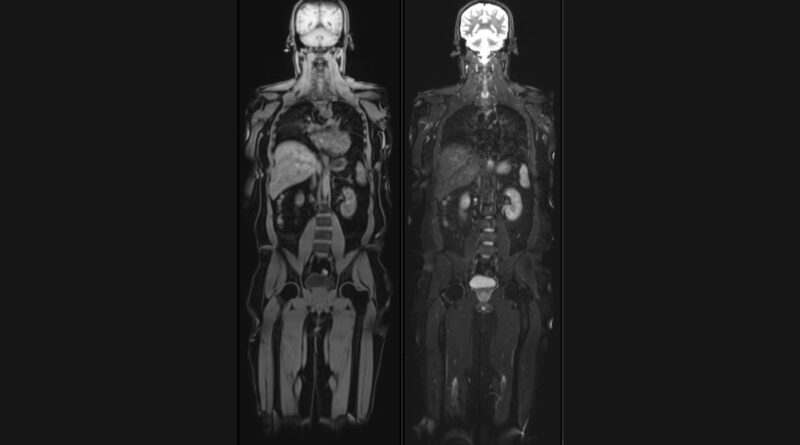

Vital Full Body MRI aims to detect potential health issues at their earliest stages, including early-stage cancers, aneurysms, spinal degeneration, disc bulges, and abnormalities in the brain, abdomen, and chest. The scans utilize cutting-edge technology to provide detailed, high-resolution images, enabling early diagnosis and intervention, thereby improving treatment outcomes.

Unique offerings of Vital MRI are – Brain volume analysis, Liver fat and Visceral fat quantification by MRI and Calcium scoring CT to assess heart attack risk. Brain volumetry analysis, generating a ‘Brain Age’ report that compares an individual’s brain health to their chronological age. This valuable insight can help individuals understand their cognitive well-being and take proactive measures to maintain brain health and prevent dementia.